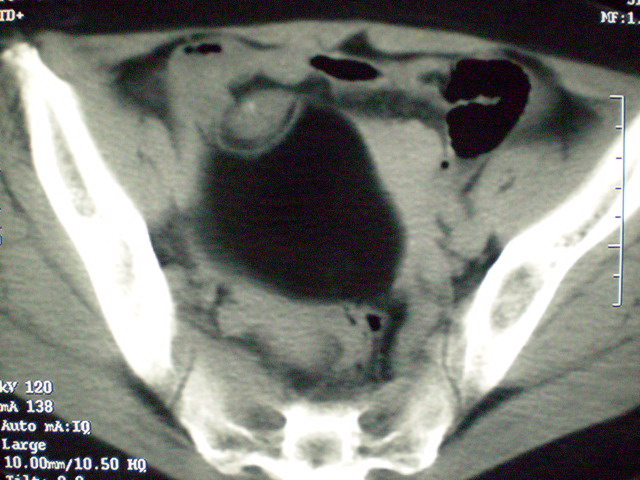

f 60y,b超提示脂肪瘤.[img][/img]

右侧附件囊性畸胎瘤,三种组织均见.

那个高密度灶形状好象牙齿。典型,收藏了

脂肪密度肿块,内可见团块状影,典型皮样囊肿

的确比较典型的畸胎瘤!不过,应该确切的说是盆腔畸胎瘤,右侧附件来源的可能性比较大。